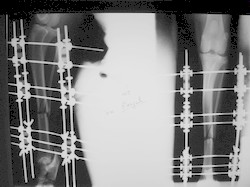

PRÁCTICAS CURSO DE FIJACIÓN EXTERNA PERFECCIONAMIENTO.

Elongacion.